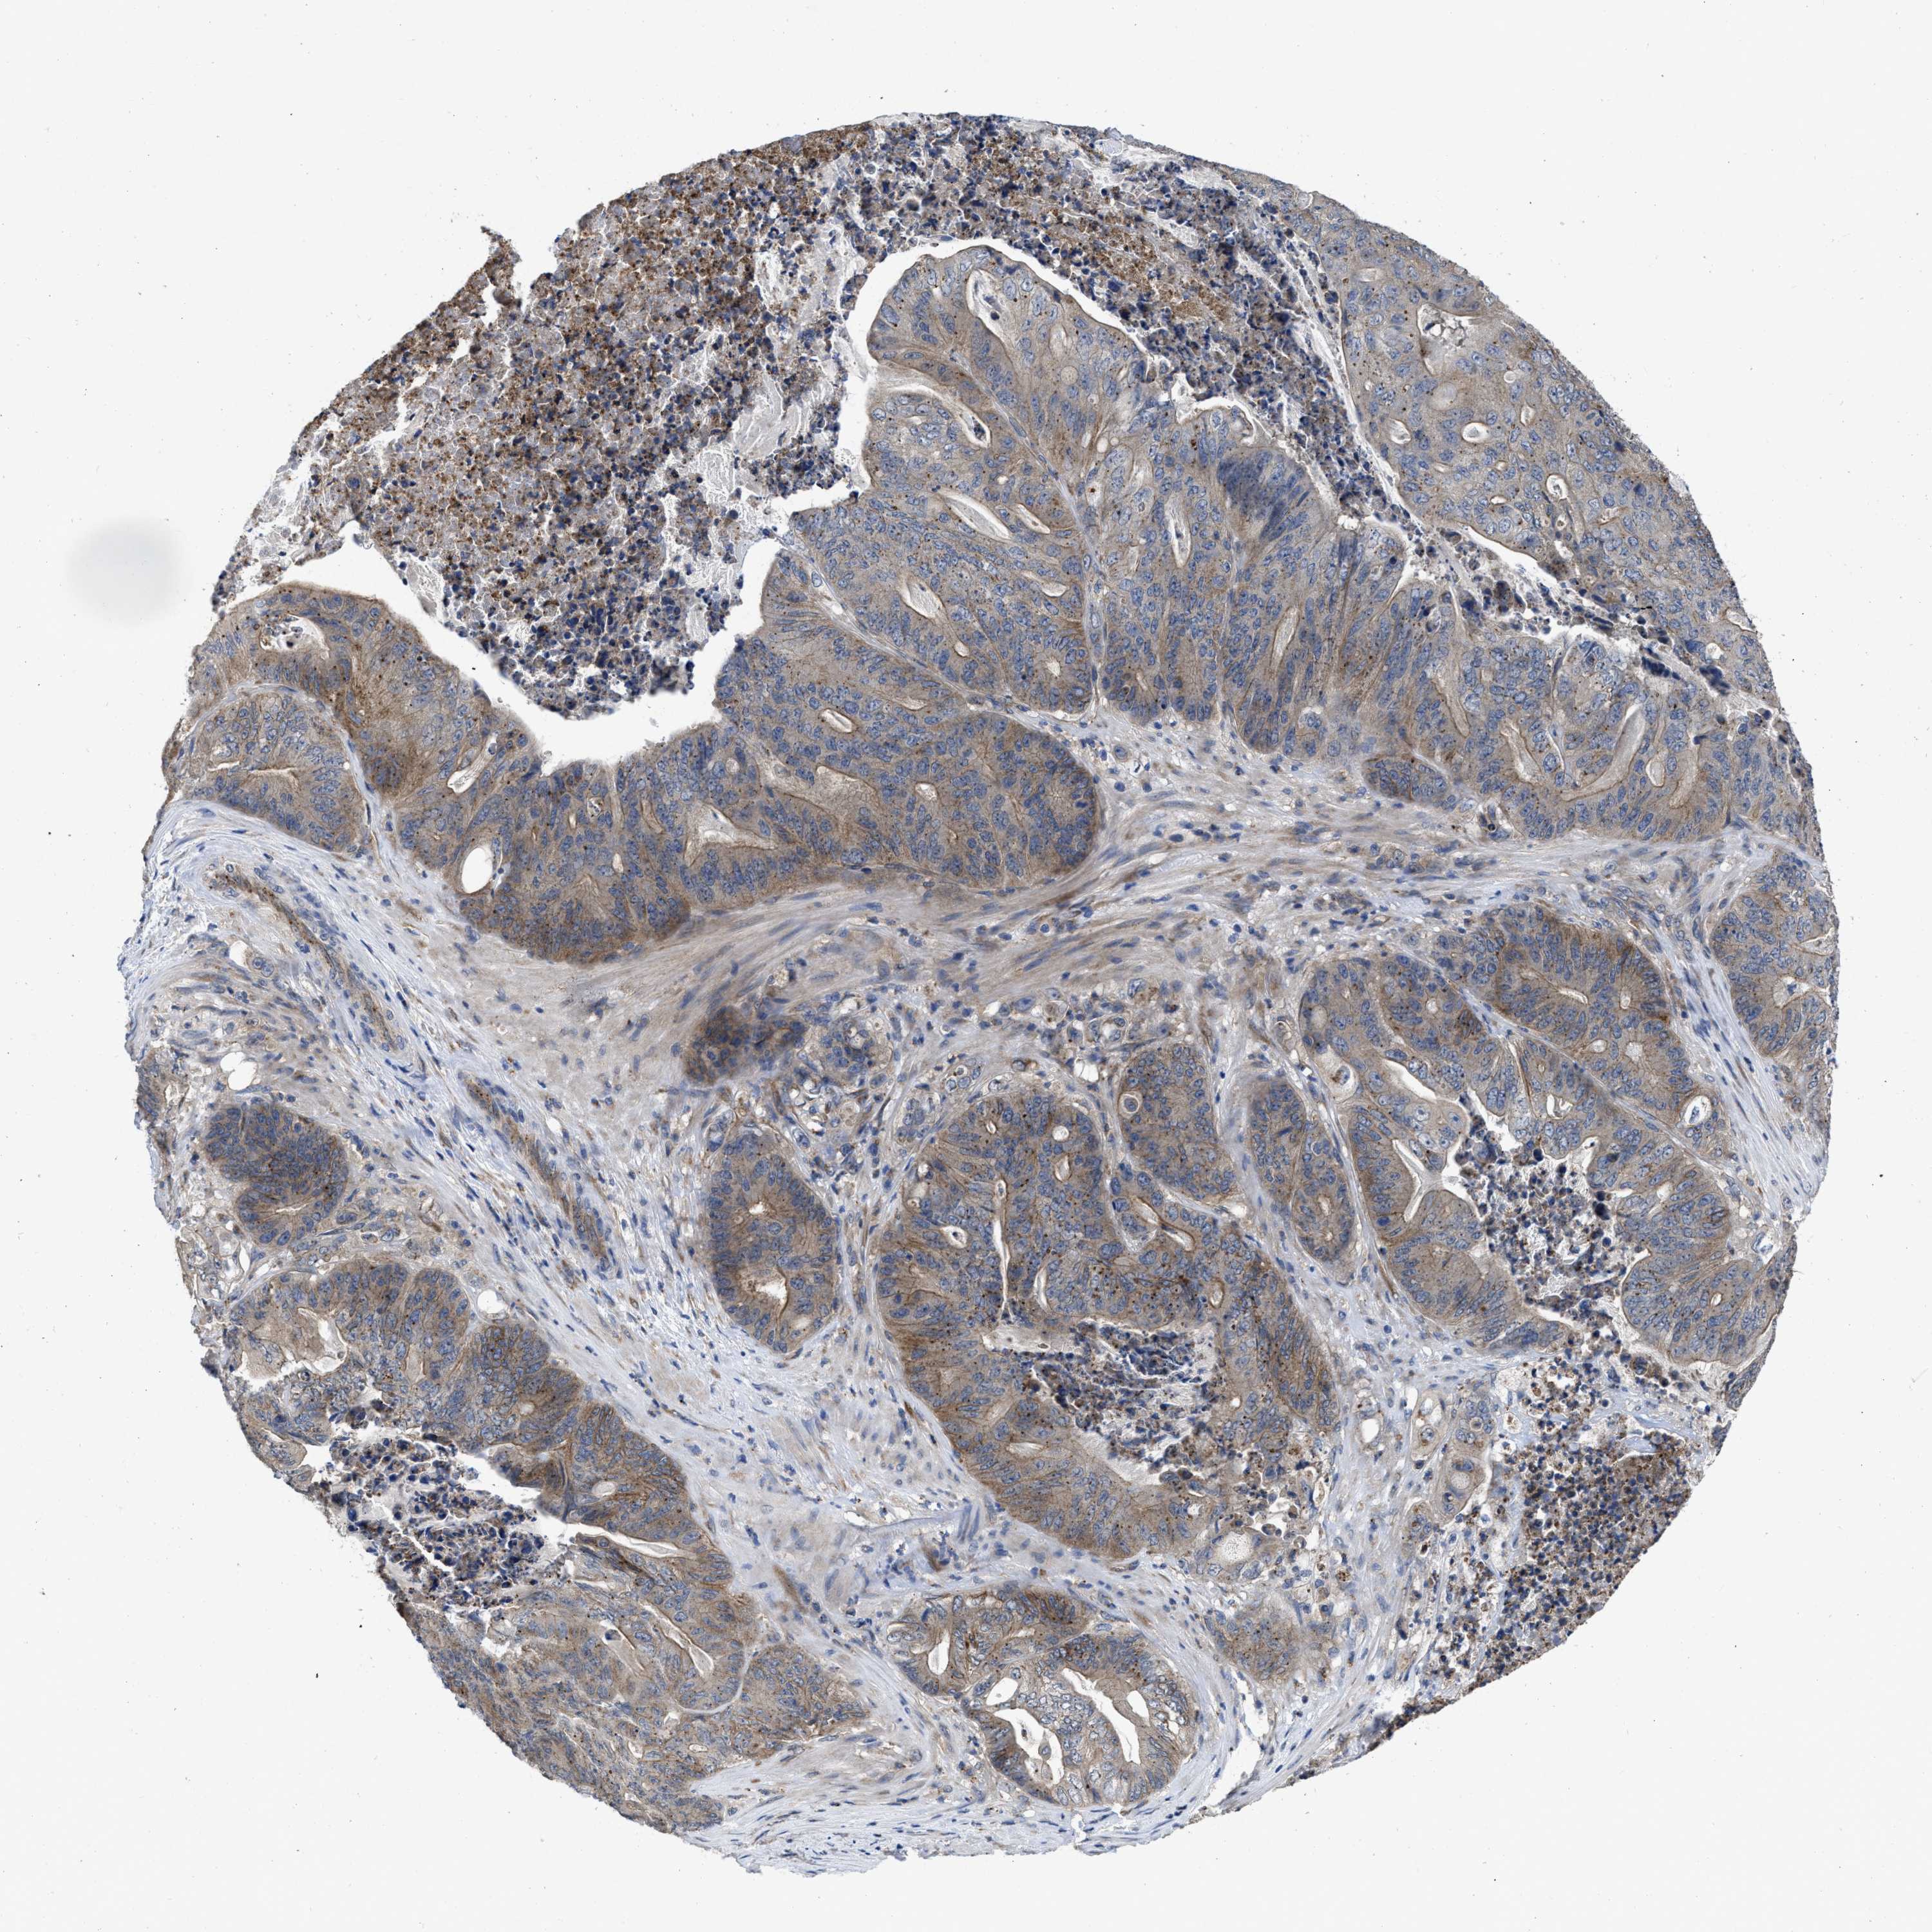

STOMACH CANCER - Protein expressioni

A mouse-over function shows sample information and annotation data. Click on an image to view it in a full screen mode. Samples can be filtered based on level of antibody staining by selecting one or several of the following categories: high, medium, low and not detected. The assay and annotation is described here.

Note that samples used for immunohistochemistry by the Human Protein Atlas do not correspond to samples in the TCGA dataset.

Antibody stainingi

Antibody staining in the annotated cell types in the current human tissue is reported as not detected, low, medium, or high, based on conventional immunohistochemistry profiling in selected tissues. This score is based on the combination of the staining intensity and fraction of stained cells.

Each image is clickable and will lead to virtual microscopy that enables deeper exploration of all samples and also displays staining intensity scores, fraction scores and subcellular localization as well as patient and tissue information for each sample.

Antibody HPA015794

Antibody CAB004544

Staining

High

Medium

Low

Not detected

Intensity

Strong

Moderate

Weak

Negative

Quantity

>75%

75%-25%

<25%

None

Location

Nuclear

Cytoplasmic/membranous

Cytoplasmic/membranous,nuclear

Adenocarcinoma, NOS

Adenocarcinoma, High grade